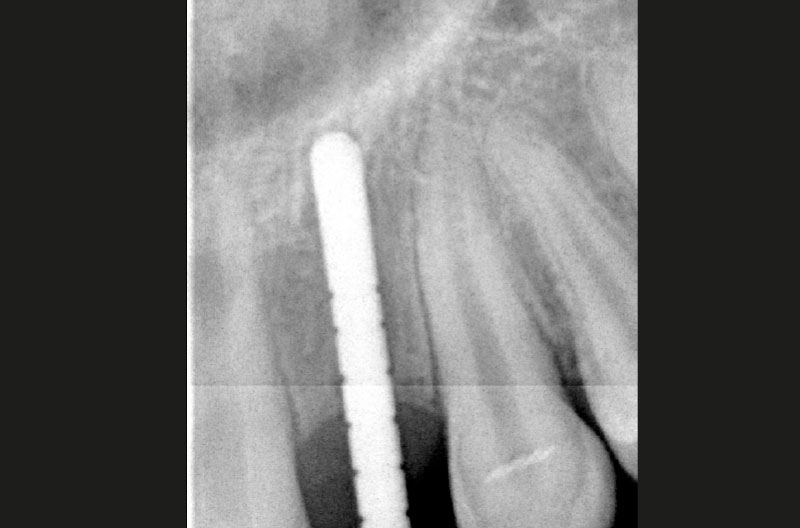

Dopo aver praticato l’anestesia plessica sia vestibolarmente che palatalmente, si esegue un lembo rettangolare a spessore totale senza interessare le papille (Figg. 2, 3). Una volta scollati i tessuti si utilizza una fresa a lancia per la corticotomia avendo cura di creare un invito più palatale, in considerazione della grossa concavità presente sulla parete vestibolare, ma tenendo in considerazione il futuro profilo di emergenza dell’impianto (Fig. 4). Dopo il passaggio con la fresa pilota, ad una profondità di 11 mm, si inserisce nel sito un misuratore di profondità e si esegue una RX di controllo per verificare il corretto parallelismo con i denti contigui e controllare la profondità di lavoro (Figg. 5-7).

Le RX di controllo confermano il corretto posizionamento sia dell’impianto in zona 22 che dei due ExaConnect e delle due corone provvisorie avvitate (Figg. 44, 45).